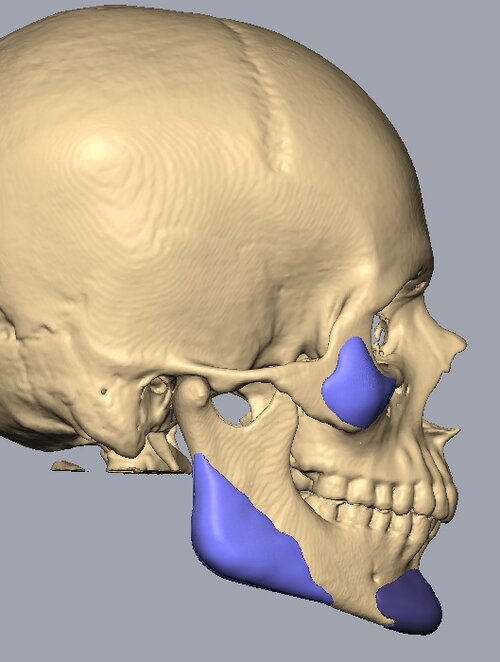

Recieved the draft 1 of the design, what changes should i ask for?? a couple of things i can think of are malar implants not giving enough lateral protrusion, gonion flaring.

I also am planning to include infra implants as well.